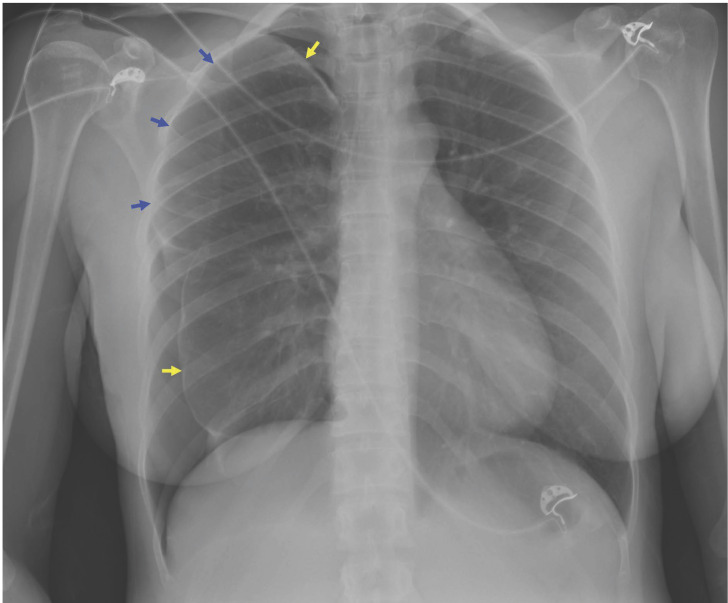

Catamenial pneumothorax is a spontaneous recurrent pneumothorax that occurs in women of reproductive age and in temporal relationship with the menses. It usually occurs within 24 hours before or 72 hours after the start of the menstrual cycle; however, multiple variations have been described in terms of the temporal relationship. To date, it is considered a rare condition; this may be justified by the limited available knowledge on this disease leading to misdiagnosis. Often, making a diagnosis of catamenial pneumothorax is complicated; it mainly depends on the medical history; also, it may be a surgical or histopathological diagnosis. Management strategies for catamenial pneumothorax may include combinations of hormonal therapy, pleurodesis, lung parenchyma resection, and diaphragm resection/repair. The aim of reporting this atypical case of catamenial pneumothorax is to highlight the relevance of having the adequate knowledge on this entity so it does not go unnoticed despite its apparent low incidence.